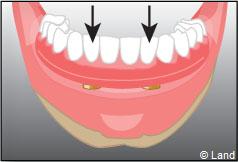

Les implants peuvent aussi servir à stabiliser un appareil amovible au maxillaire supérieur comme au maxillaire inférieur. Dans ce cas, les implants retiennent la prothèse amovible par des systèmes d’attachement.

Deux techniques sont possibles. Elles font appel à la barre de rétention ou aux boutons-pressions.